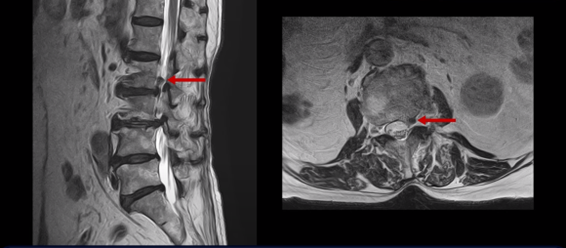

또 위로 올라가서 2번 3번 관절을 보면 왼쪽으로 디스크가 파열되어 위로 밀려 올라가있고

3번 4번 마디를 보면 왼쪽으로 디스크가 많이 밀려나와 있습니다.

이 두 마디가 왼쪽 증상, 특히 허벅지 통증을 일으키는 원인으로 보입니다. 이렇게 여러 마디가 안 좋을수록, 또 고령일수록 수술하기가 더 까다로워지는데 또 큰 문제는 이 환자분은 근감소증이 심하게 진행된 상태로, 여기 MRI에서 보시다시피 허리 하부의 기립근 근육이 전부 지방으로 변해버려 근육 자체가 거의 없는 상태인 것입니다.